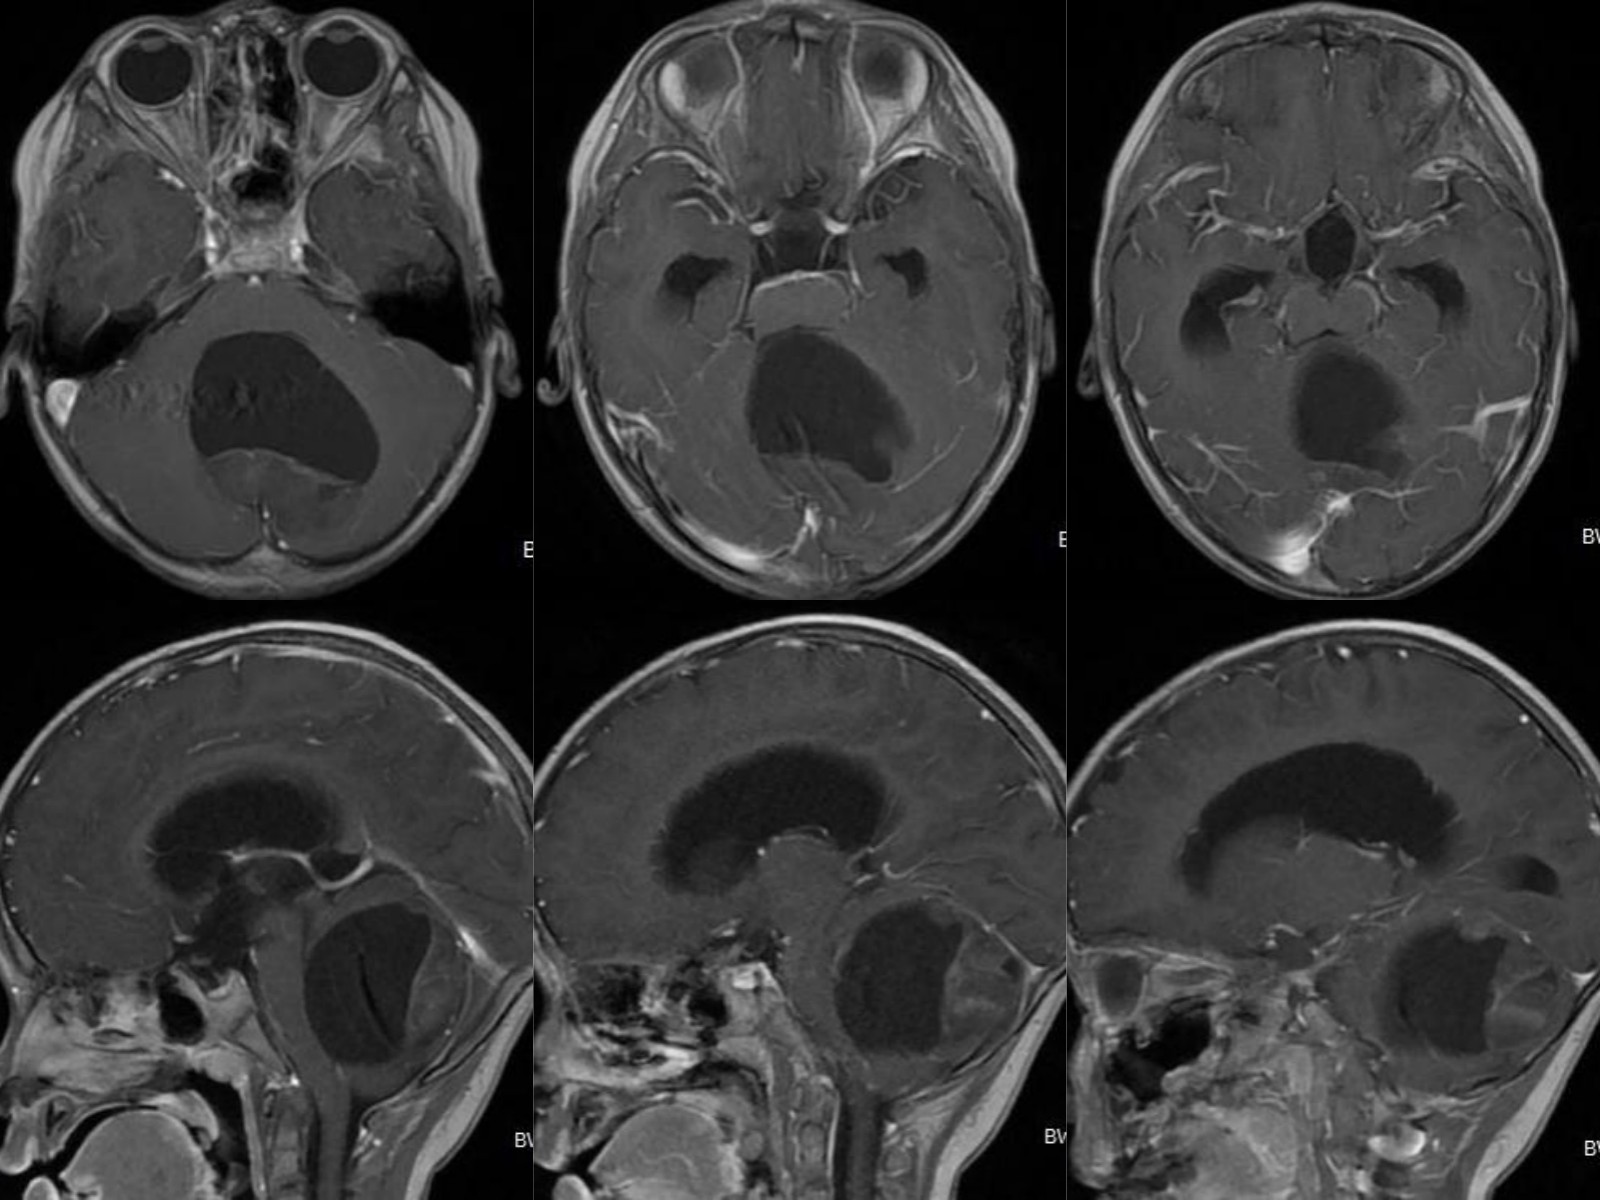

完善术前检查后,在全麻下行后正中入路后颅凹肿瘤切除术,手术顺利。术后复查磁共振示肿瘤全切。病理确诊毛细胞星形细胞瘤。患儿术后恢复良好,步态平稳,双手抓物稳准。术后10天出院。

图3 术后CT、MR示肿瘤全切无残留,中脑导水管通畅。